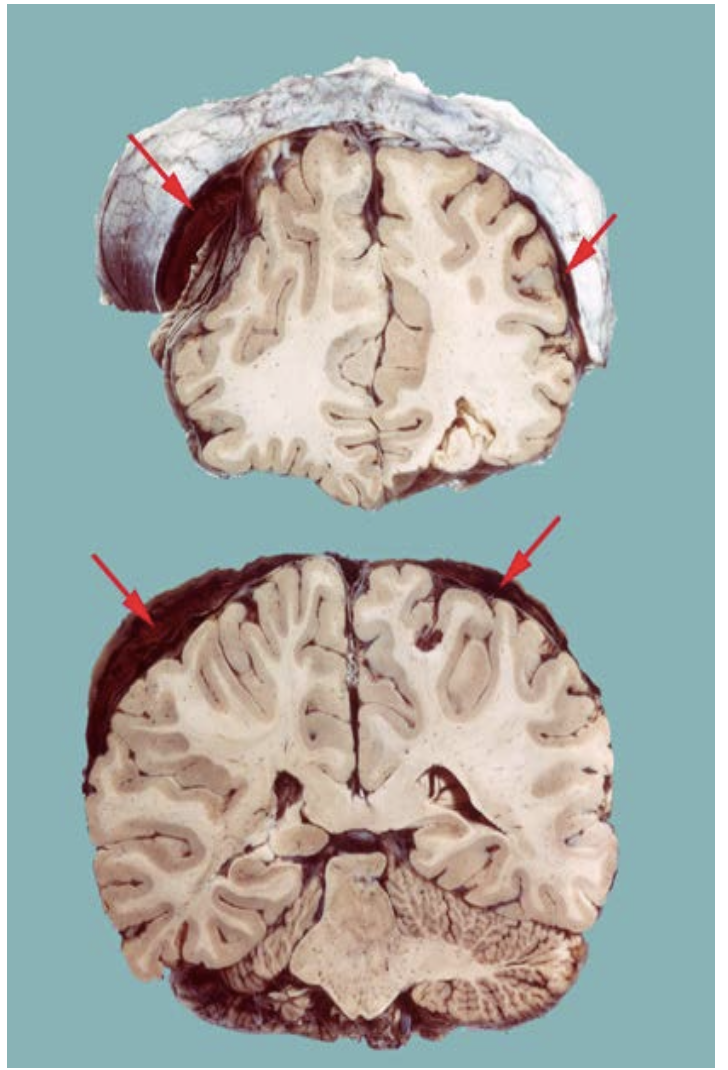

Cerebral Contusion

Area of hemorrhagic necrosis

– Usually affects the crest of gyri.

– Frequently seen in subfrontal and anterior temporal lobes as the base of the brain slides over the irregular skull base (arrows).

Blood is removed by macrophages leaving an irregular tan discoloration. (circle)